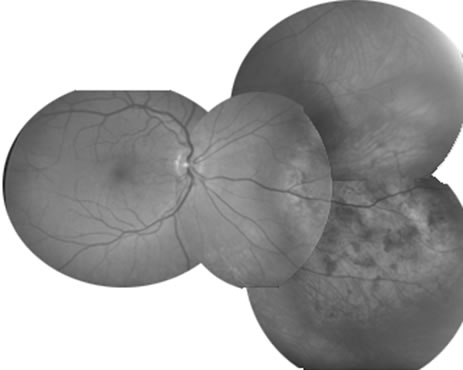

Necrotic melanomas account for approximately 5% of uveal melanomas; in the majority of cases, there is intraocular inflammation accompanying the cataract.7–9Figures 1 and 2 demonstrate a typical case. The patient had a long history of unilateral decreased vision. The eye had become painful 1 month before admission, and he was referred for evaluation of uveitis. Clinically, there was a dense, unilateral cataract with significant intraocular inflammation, which was manifested as a ciliary flush with 2+ cells and flare. Media opacity obscured all fundus detail. An immersion B-scan demonstrated a large intraocular tumor that was most consistent with a uveal melanoma. The eye was removed, and the diagnosis was confirmed histologically.10

|

|